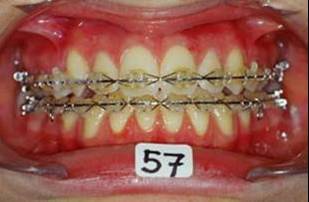

En fouillant dans mes cas j'ai trouve celui ci qui presente une beance assez importante. Je me suis rappele qu'un certain message etait lance il y a qq temps a propos d'un enfant qui presente une beance et de savoire comment faire dans ce cas. Je pense qu'il est interessant de voir comment les uns et les autres prennent en charge ce type de cas. Il s'agit d'un fille de 12 ans, succion de pouce, interposition linguale totale, beance de molaire a molaire, respiration mixte, incompetence labiale au repos, fonction labiale serree. Le total quoi!!! Voici la premiere serie de photos

4- Collage de l'arcade sup, presque 6 mois apres et voici le photo apres seance de college

Collage bas fait presque 3 mois apres le haut, avec des elastiques verticaux pendant 3 semaines seulement. Et voici les photos, la suite je vous en passe car il s'agit de simple finition.

P.S. photos au moment du collage bas